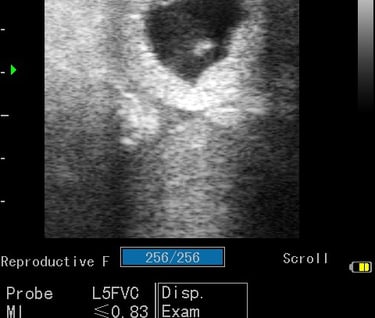

Gynécologie